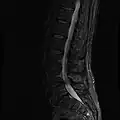

MRI

-

MRI lumbar spine with degeneration (sagittal T2 FRFSE) -

MRI lumbar spine with degeneration (sagittal T1 FSE) -

MRI lumbar spine with degeneration (sagittal FAST STIR) -